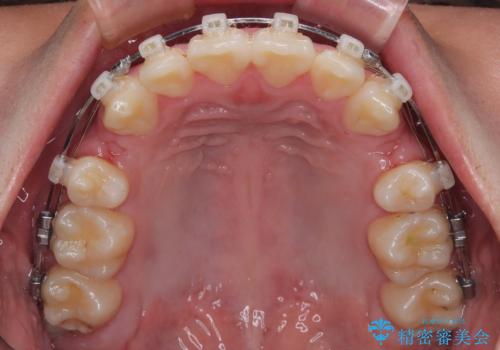

- クリアブラケット

- 1年6ヶ月

特に前歯のデコボコが顕著であり、上下左右第一小臼歯の4本を抜歯し、ワイヤー装置を使用して咬み合わせ高さを改善しながら、歯列を整えて行くこととしました。

移動が順調に進み、1年半の短期間で治療を終えることができました。

前方に突出した上顎前歯の傾斜も改善されました。